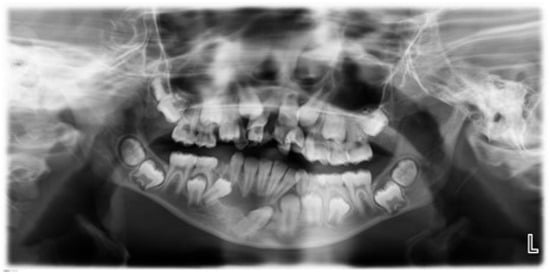

Incidental Pathologic Findings from Orthodontic Pretreatment Panoramic Radiographs

3. Results